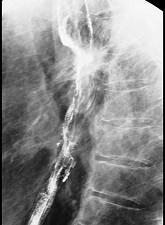

问题 女性患者,67岁进行性吞咽困难半年,X线及CT检查如图,应诊断为 ( )

选项 A.食管癌 B.食管憩室 C.食管炎 D.食管良性狭窄 E.食管静脉曲张

答案 A